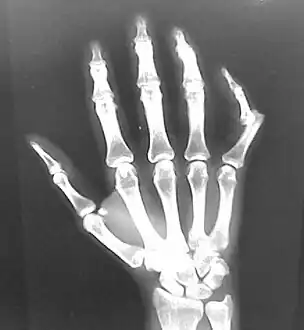

Dislocation of the left index finger

Radiograph of left index finger dislocation